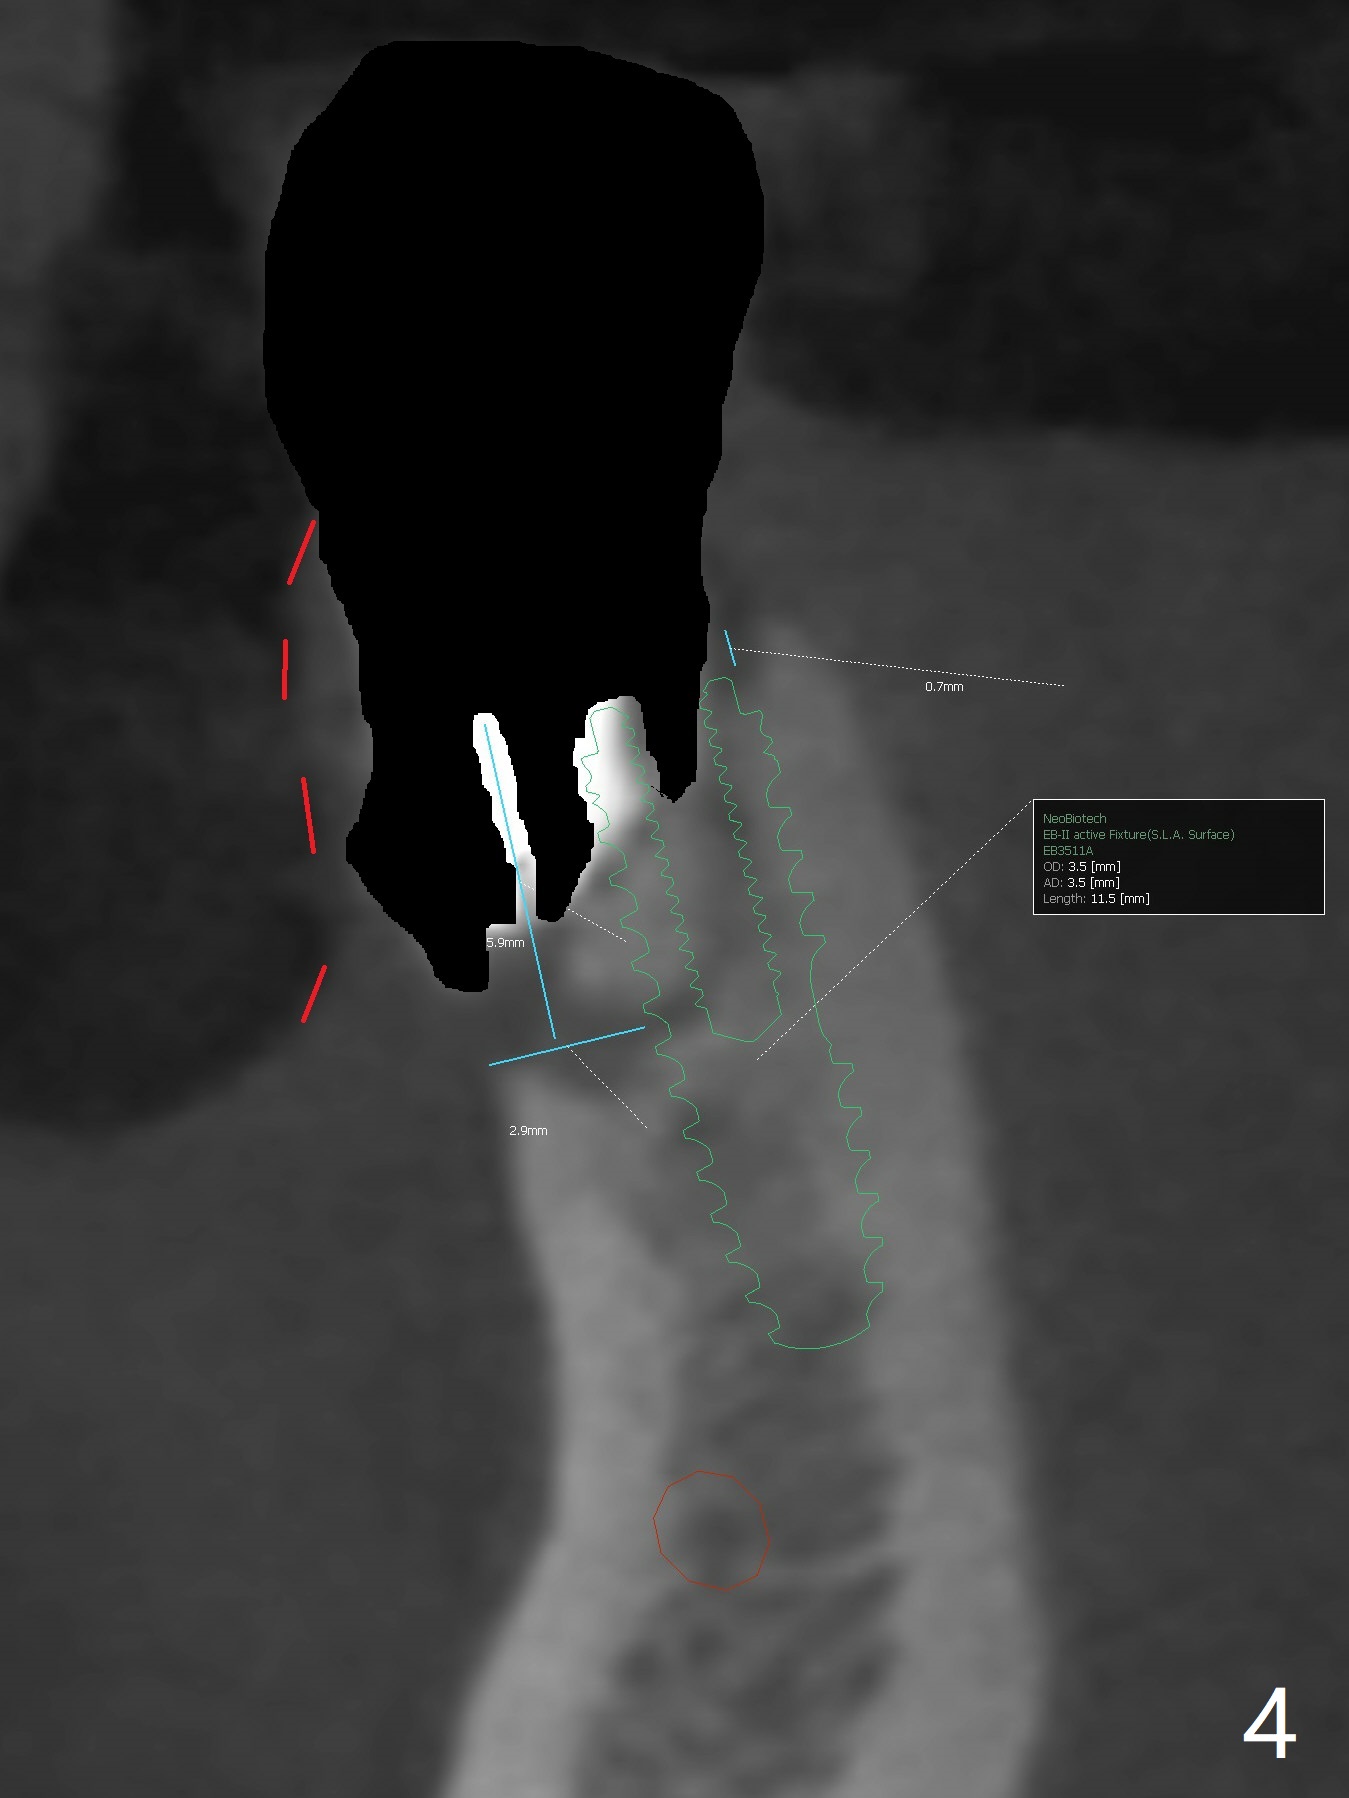

A -year-old man seeks treatment for the tooth #28 with severe bone loss (Fig.1 islands of bone remaining in the mesial surface of the tooth #27, reossification center for grafted bone). The tooth #28 has oblique root fracture (Fig.2 lingual view). One of treatment options is to place an immediate implant (green) at #28 as lingual as possible (Fig.3,4 (coronal section, after extraction (black area))). Sticky bone is placed buccal (Fig.5 red); some of bone graft will be pressed into the space between implant threads (arrowheads, bone and implant contact area expectedly to be higher than delayed placement due to less pressure to the native bone). In spite of severe bone loss between #27 and 28 (Fig.6 (sagittal section) after extraction), the crestal bone appears to exist in the mesial surface of #27 (*). With placement of an abutment (Fig.7 pink) and an immediate provisional (white), bone graft is packed as high as supracrestal (red). Restoration of the crest is expected to be better than socket preservation.

The ridge at #30 is narrow (~ 4 mm buccolingual and ~7 mm mesiodistal, Fig.8). A 4x11.5 mm will be placed. Impression will be taken for guides for #28 and 30. Incision will be made prior to guide seating (Fig.9 occlusal view); initial osteotomy (Fig.10 black circle) will be conducted with guide clockwise (white curved arrow). With removal of the guide, the ridge is split (Fig.11 black line). Osseocondensation drills will be used for ridge expansion with the help of guide (in the middle of the metal sleeve, Fig.12 counterclockwise).